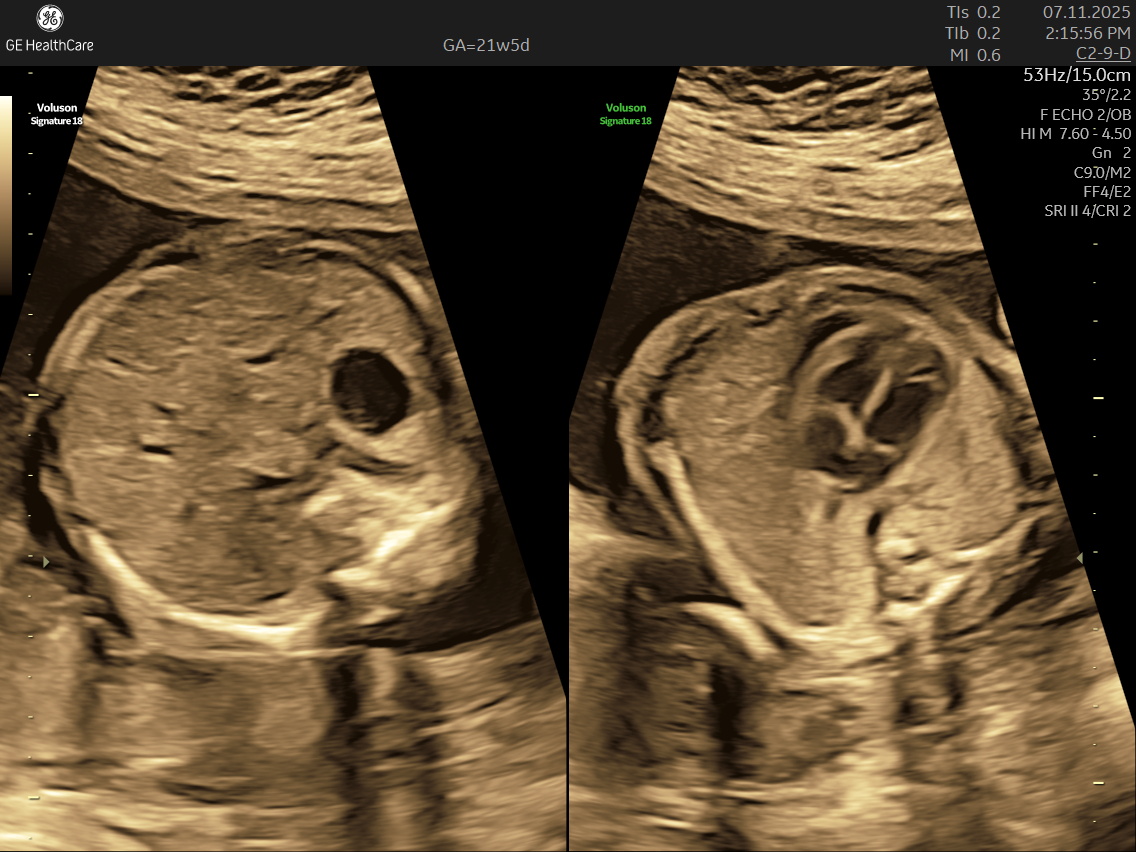

IMAGE GALLERY